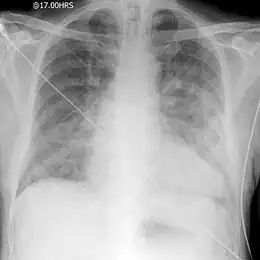

Une radiographie pulmonaire standard permet de rechercher :

• une cardiomégalie, c'est-à-dire une augmentation de taille de la silhouette cardiaque (son absence est possible) ;

• un syndrome alvéolaire ;

• des lignes de Kerley B ;

• parfois un épanchement pleural ;

• des opacités alvéolaires, floconneuses, généralement bilatérales et symétriques, souvent systématisées para-hilaires « en ailes de papillon », parfois diffuses (mais peuvent être unilatérales et asymétriques).